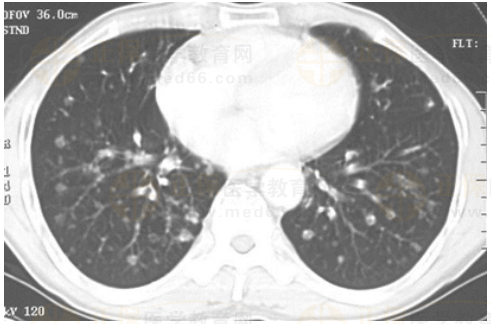

02卷-3.男性,55歲,結(jié)腸癌術(shù)后2年。

A.大葉性肺炎

B.浸潤(rùn)性肺結(jié)核

C.原發(fā)性肺癌

D.肺轉(zhuǎn)移癌

本題答案:D

【該題針對(duì)“ CT-肺癌 ”知識(shí)點(diǎn)進(jìn)行考核】